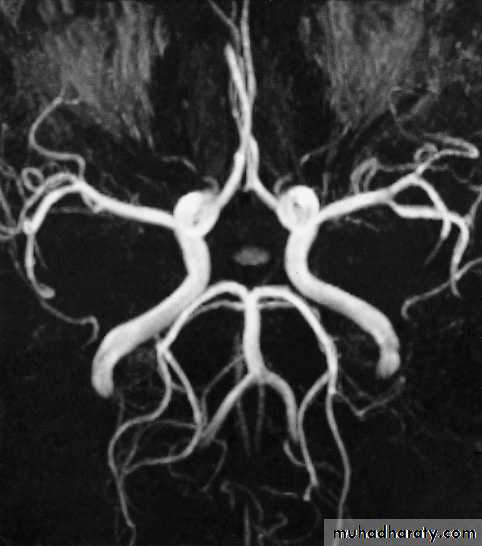

• It is possible to recognize flowing blood and, therefore, the larger arteries and veins stand out clearly without the need for contrast medium.

• MRA and MRV, Recent advances of MRI: perfusion, diffusion, spectroscopy, functional MRI, and tractography